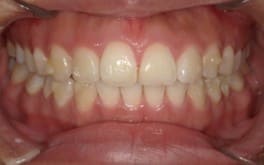

ワイヤー矯正

クリアブラケットを選択された患者様はホワイトワイヤーと透明ゴムを使用することで、見た目が目立ちにくくなります。また、各色カラーゴムもご用意しており、追加料金はかからずに選んでいただけます。

藤沢デンタルオフィスのワイヤー矯正 藤沢デンタルオフィスのワイヤー矯正